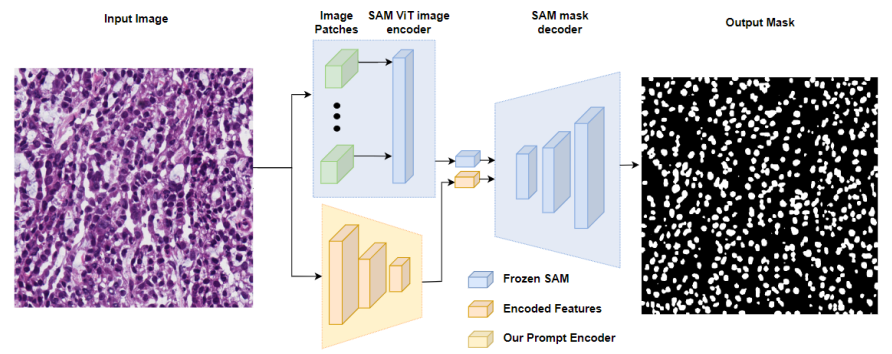

- Adapting through Auxiliary Prompt Encoder

AutoSAM:为SAM的提示生成了一个完全自动化的解决方案,基于输入图像由AutoSAM辅助提示编码器网络生成替代提示。AutoSAM 与原始的 SAM 相比具有更少的可训练参数。

AutoSAM